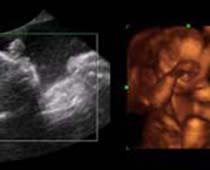

- Les Photos d'Ultrasons du visage du fétus

- 3D Photos échographie du profile du fœtus

- Les avantages cliniques de l'échographie 3D et 4D

- Définition et les Caractéristiques de Quatre Ultrasons Dimensionnels